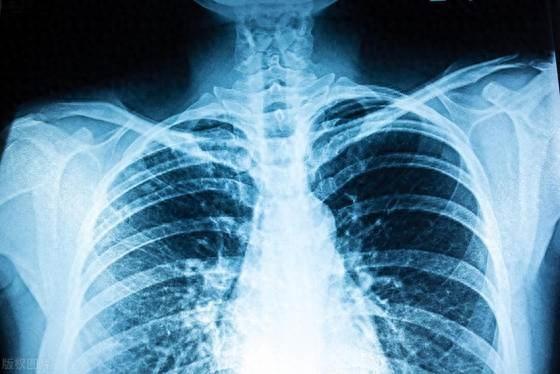

冠状动脉狭窄是一种由于血管内斑块积聚导致血流受阻的疾病,可能引发胸闷和心悸等症状,严重时甚至危及生命。其主要原因包括高脂肪饮食、缺乏运动等不良生活习惯。早期干预和改善生活方式至关重要,可有效减缓病情进展,保护心脏健康。

65岁的李大爷,退休前是一名中学教师。生活一向规律的他,在2023年初的一次常规体检中被告知血管内出现了斑块,这个消息让他颇为震惊。冠状动脉狭窄已经达到40%,医生建议他要特别注意生活习惯,否则可能需要手术干预。

随着时间推移,李大爷的症状逐渐显现出来。他发现自己偶尔会出现胸闷的情况,尤其是在爬楼梯或者快走的时候。有时候甚至会有短暂的心悸,这让他非常担心。尽管症状不算严重,但他意识到如果再不改变,可能会引发更严重的健康问题。

经过一年的努力,李大爷再次进行了详细的体检。结果显示,他的冠状动脉狭窄程度从最初的40%降低到了25%,这一显著的进步让医生都感到惊讶。李大爷自己更是感慨万分,他表示,正是这四个好习惯的养成,帮助他成功逆转了病情,重新找回了健康的生活。